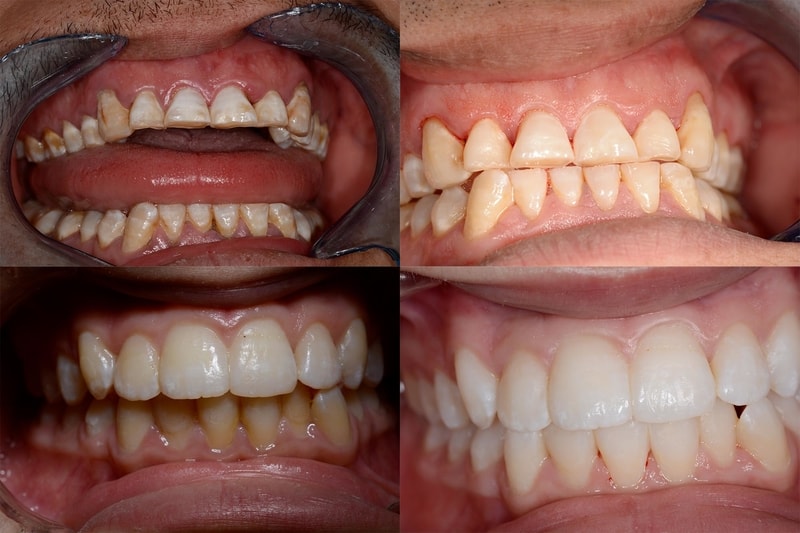

Les Usures

L’usure des dents n’est pas une maladie. Mais ce symptôme, de plus en plus fréquent et le plus souvent lié à notre hygiène de vie (alimentation, stress) et à des habitudes agressives de brossage, est difficile à prendre en charge. C’est pourquoi détecter précocement l’usure dentaire permet de corriger les facteurs aggravants.

L’usure des dents peut avoir une ou plusieurs origines.

Une origine mécanique :

L’utilisation d’une brosse à poils trop durs ou un brossage trop vigoureux qui peuvent entrainer un phénomène d’usure de l’émail.

Un brossage des dents réalisé immédiatement après avoir consommé des aliments acides.

Le bruxisme (grincer ou serrer les dents l’une contre l’autre)

Une origine chimique (on parle alors d’érosion), liés à la présence d’éléments acides dans la bouche :

La consommation excessive d’aliments ou de boissons acides tels que les sodas, l’alcool, les agrumes ou les sauces à base de vinaigre. Les médicaments comme la vitamine C ou l’aspirine dont l’acidité attaque les dents. Mais aussi certains antidépresseurs qui entrainent une réduction de la production de salive, protectrice naturelle des dents contre les attaques acides.

Certaines pathologies entrainant des vomissements et des reflux gastro-œsophagiens.

Le traitement passe tout d’abord par l’arrêt des “mauvaises” habitudes induisant les usures. Parfois il faut plusieurs séances pour que le patient trouve de quelle habitude il s’agit !

L’objectif ensuite est de protéger les dents dont l’émail a disparu en étant le plus conservateur possible ,c’est à dire en mutilant le moins possible la dent. En fonction de la sévérité de l’atteinte, les matériaux et les techniques différeront.On utilisera le plus possible des matériaux collés: des composites directs, des inlays, des overlays, des onlays, veneerlays, facettes ...